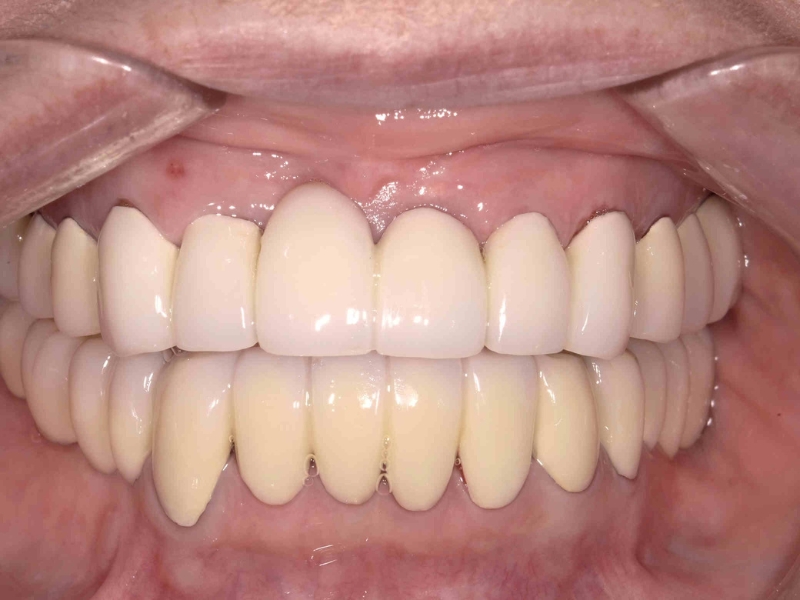

<症例2>60歳代 男性

長年放置したために歯周病が進行し噛みにくくなった患者様が、インプラントを入れ全顎的な治療を行い、審美改善しました。

正面

レントゲン写真